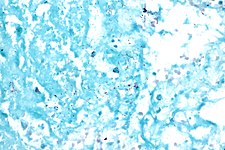

Acid fast bacilli, Ziehl–Neelsen stain.

Sputum smears and cultures should be done for acid-fast bacilli if the patient is producing sputum.[1] The preferred method for this is fluorescence microscopy (auramine-rhodamine staining), which is more sensitive than conventional Ziehl–Neelsen staining.[3] In cases where there is no spontaneous sputum production, a sample can be induced, usually by inhalation of a nebulized saline or saline with bronchodilator solution. A comparative study found that inducing three sputum samples is more sensitive than three gastric washings.[4]

Other mycobacteria are also acid-fast. If the smear is positive, PCR or gene probe tests can distinguish M. tuberculosis from other mycobacteria. Even if sputum smear is negative, tuberculosis must be considered and is only excluded after negative cultures.[citation needed]